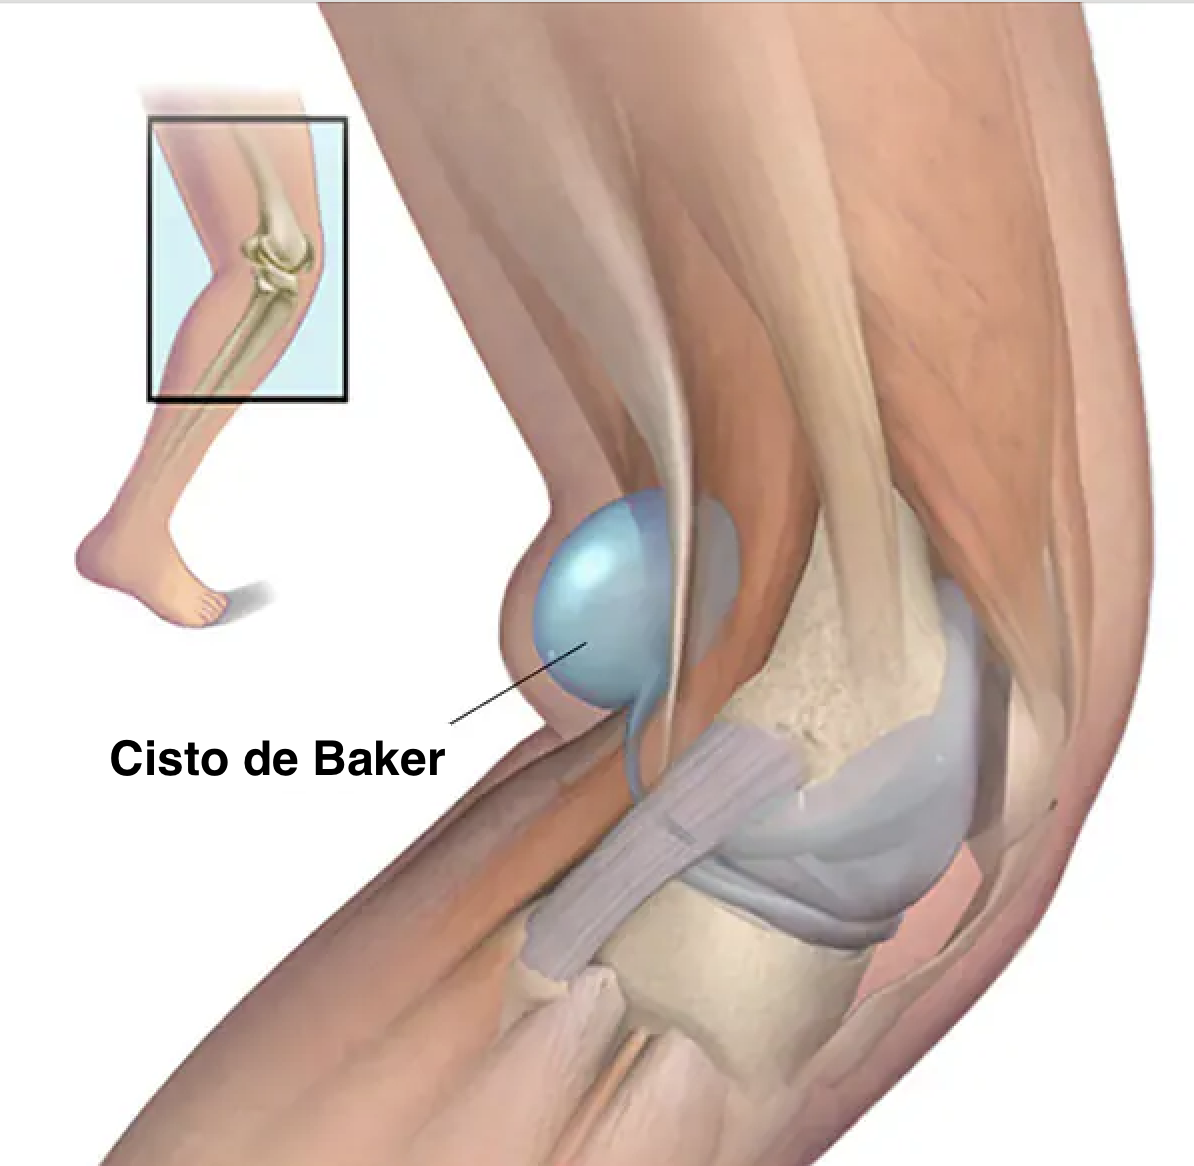

O cisto de Baker é um acúmulo de líquido sinovial na parte de trás do joelho, geralmente localizado entre o tendão do músculo semimembranoso e a cabeça medial do gastrocnêmio. Esse líquido vem da própria articulação do joelho e se acumula nessa região quando há aumento de pressão intra-articular ou inflamação persistente.

O joelho produz líquido sinovial para lubrificação e nutrição da articulação. Quando existe artrose, meniscopatia, sinovite ou outra alteração inflamatória, a produção de líquido pode aumentar. Parte desse líquido pode passar para a bursa gastrocnêmio-semimembranosa e ficar retido ali por um mecanismo semelhante a uma válvula de sentido único.

Esse fenômeno explica por que o cisto pode aumentar de tamanho ao longo do tempo, principalmente quando a doença de base não é tratada.